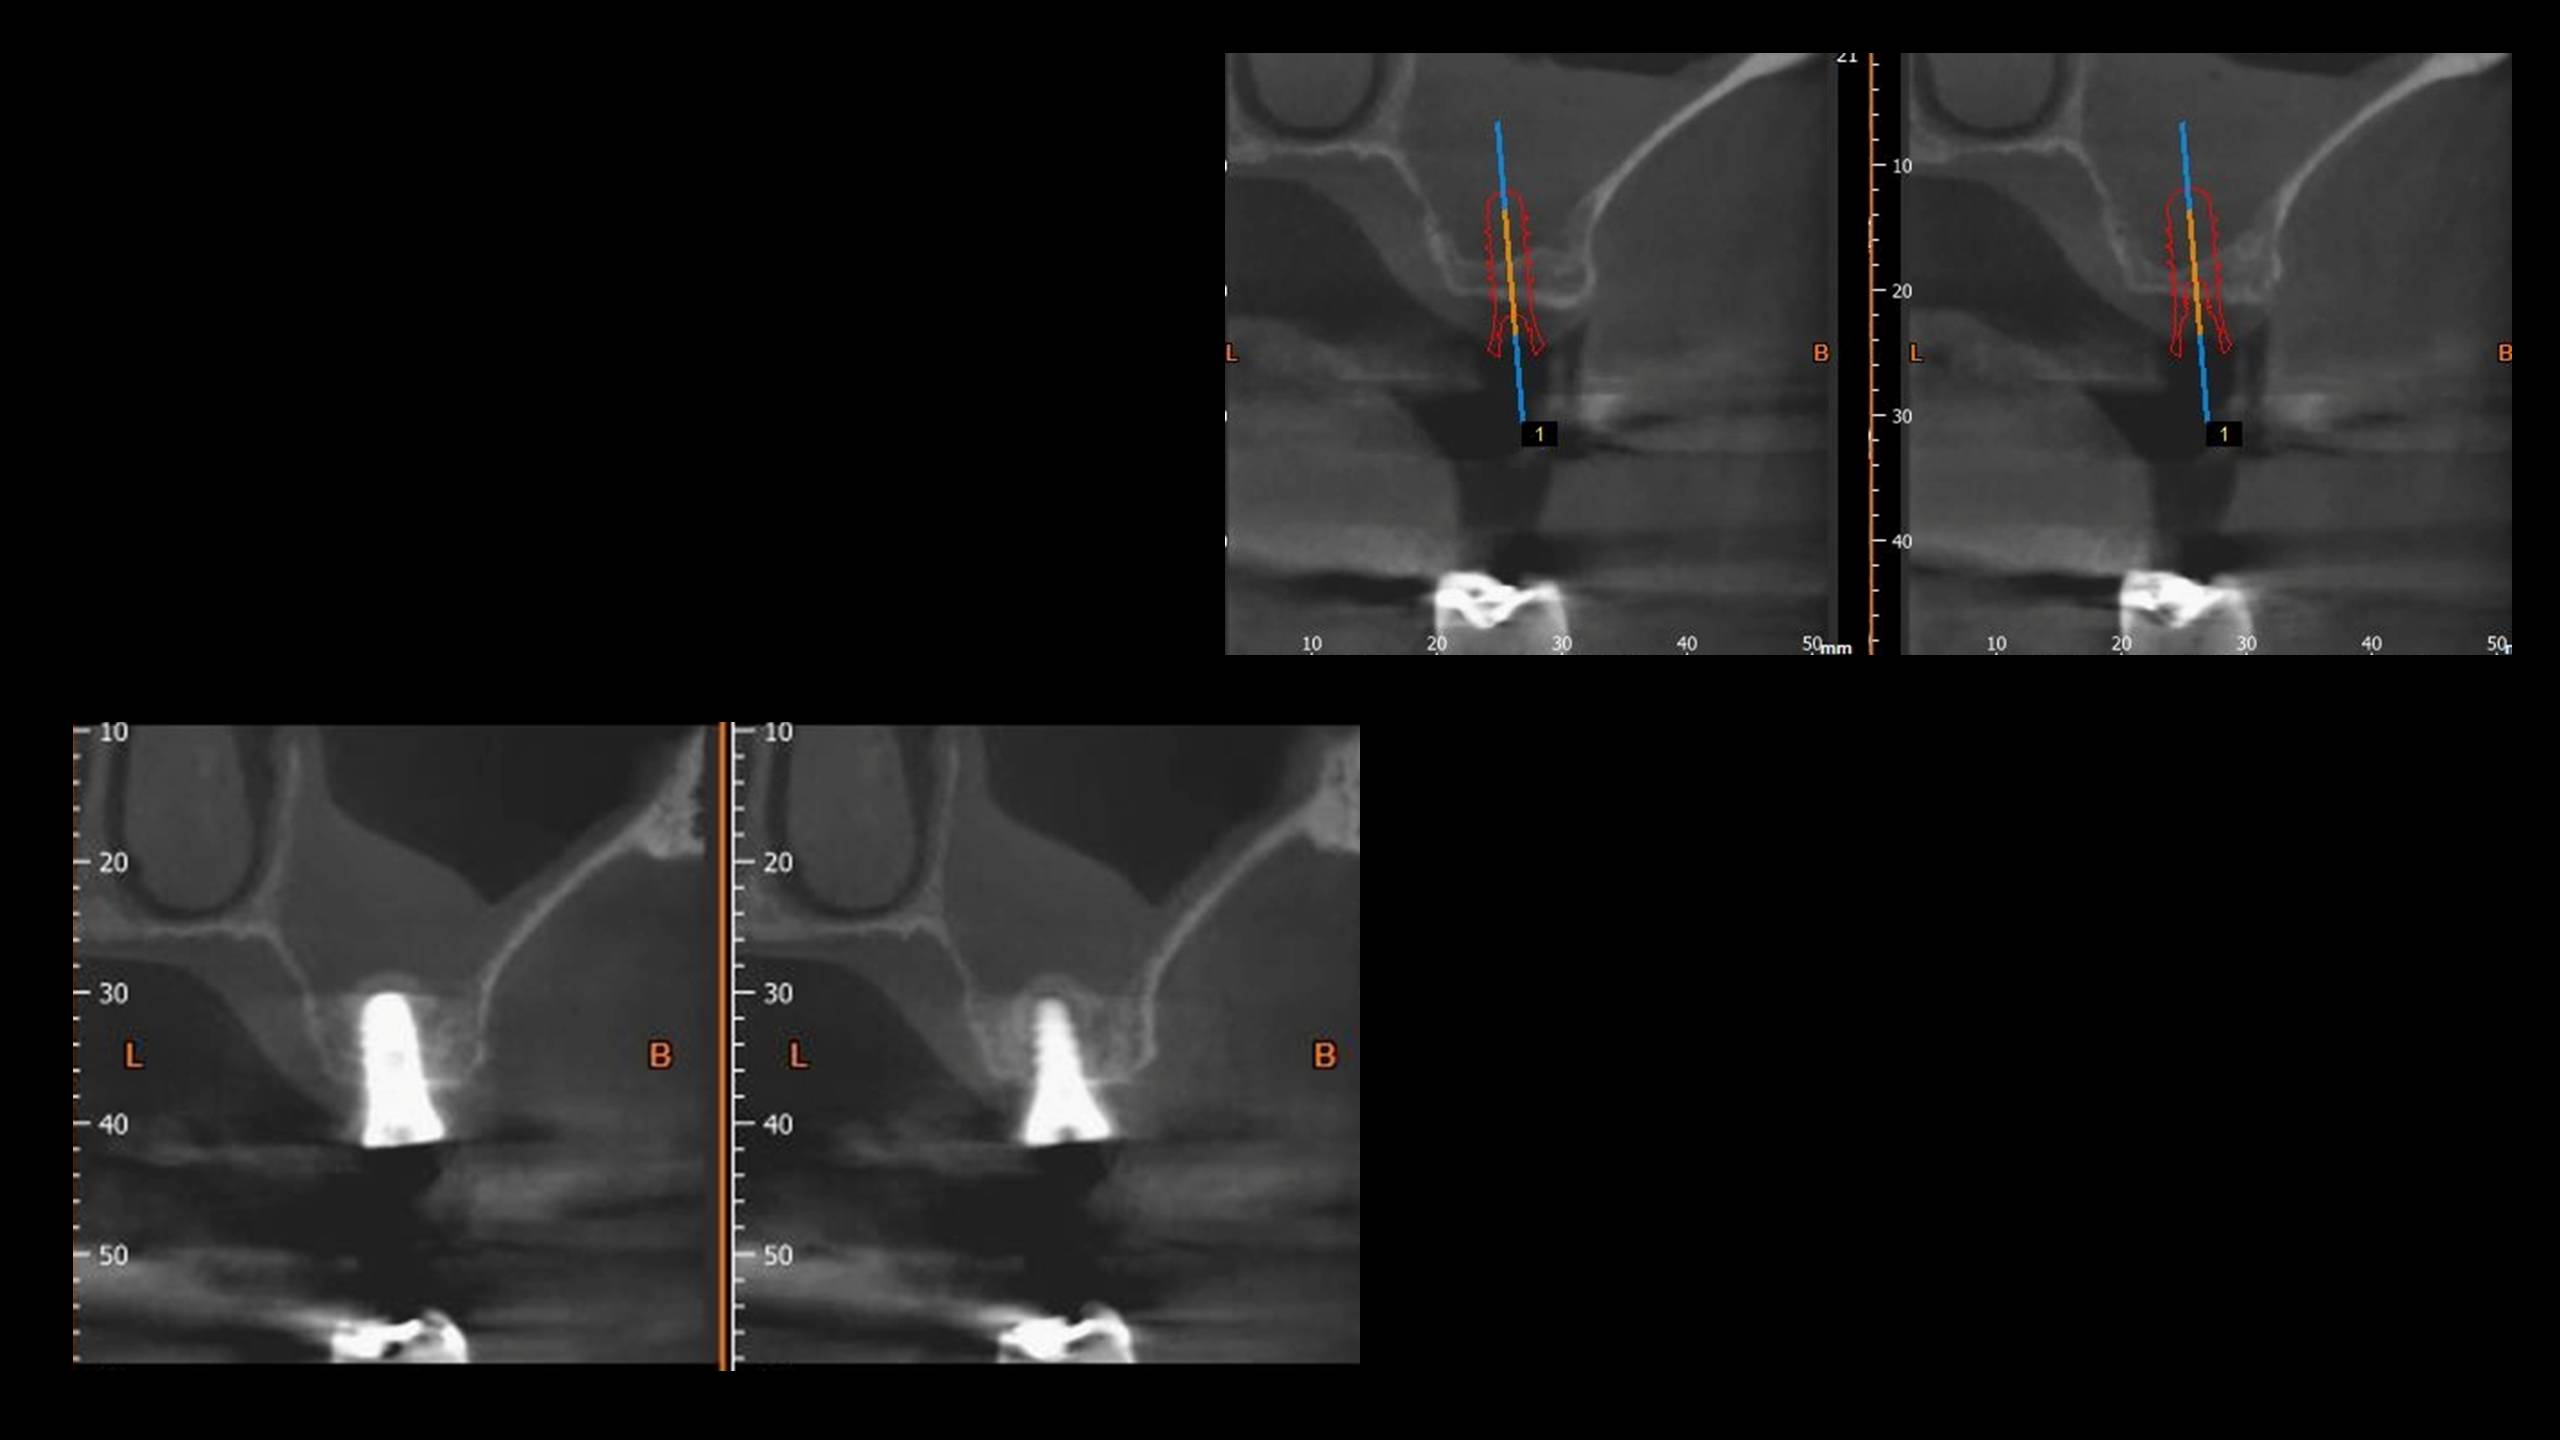

CBCT avant et après la pose combinée au comblement et à l’élévation du plancher sinusien.

Évolution radiologique d’un environnement osseux péri-implantaire après un protocole d’extraction puis implantation.

Évolution radiologique d’un environnement osseux péri-implantaire après un protocole d’extraction, puis implantation/comblement sinusien. Notez le gain osseux après seulement 6 mois.